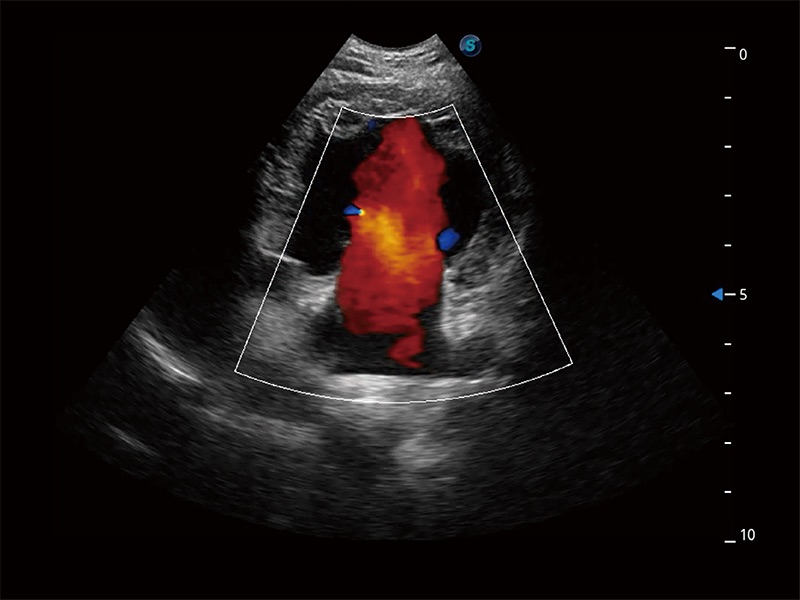

在传统二维血流成像的基础上,呈现血流的立体感,具有动感的生命力之美。即便是微小的血管也能轻松应对,提高了血流的视觉敏感性。

ProPet 80 配备了丰富的心脏探头群、先进的成像技术和专业的心脏测量工具,可帮助动物医生为不同体型和生理结构的动物提供心脏和心肌功能的全面评估。